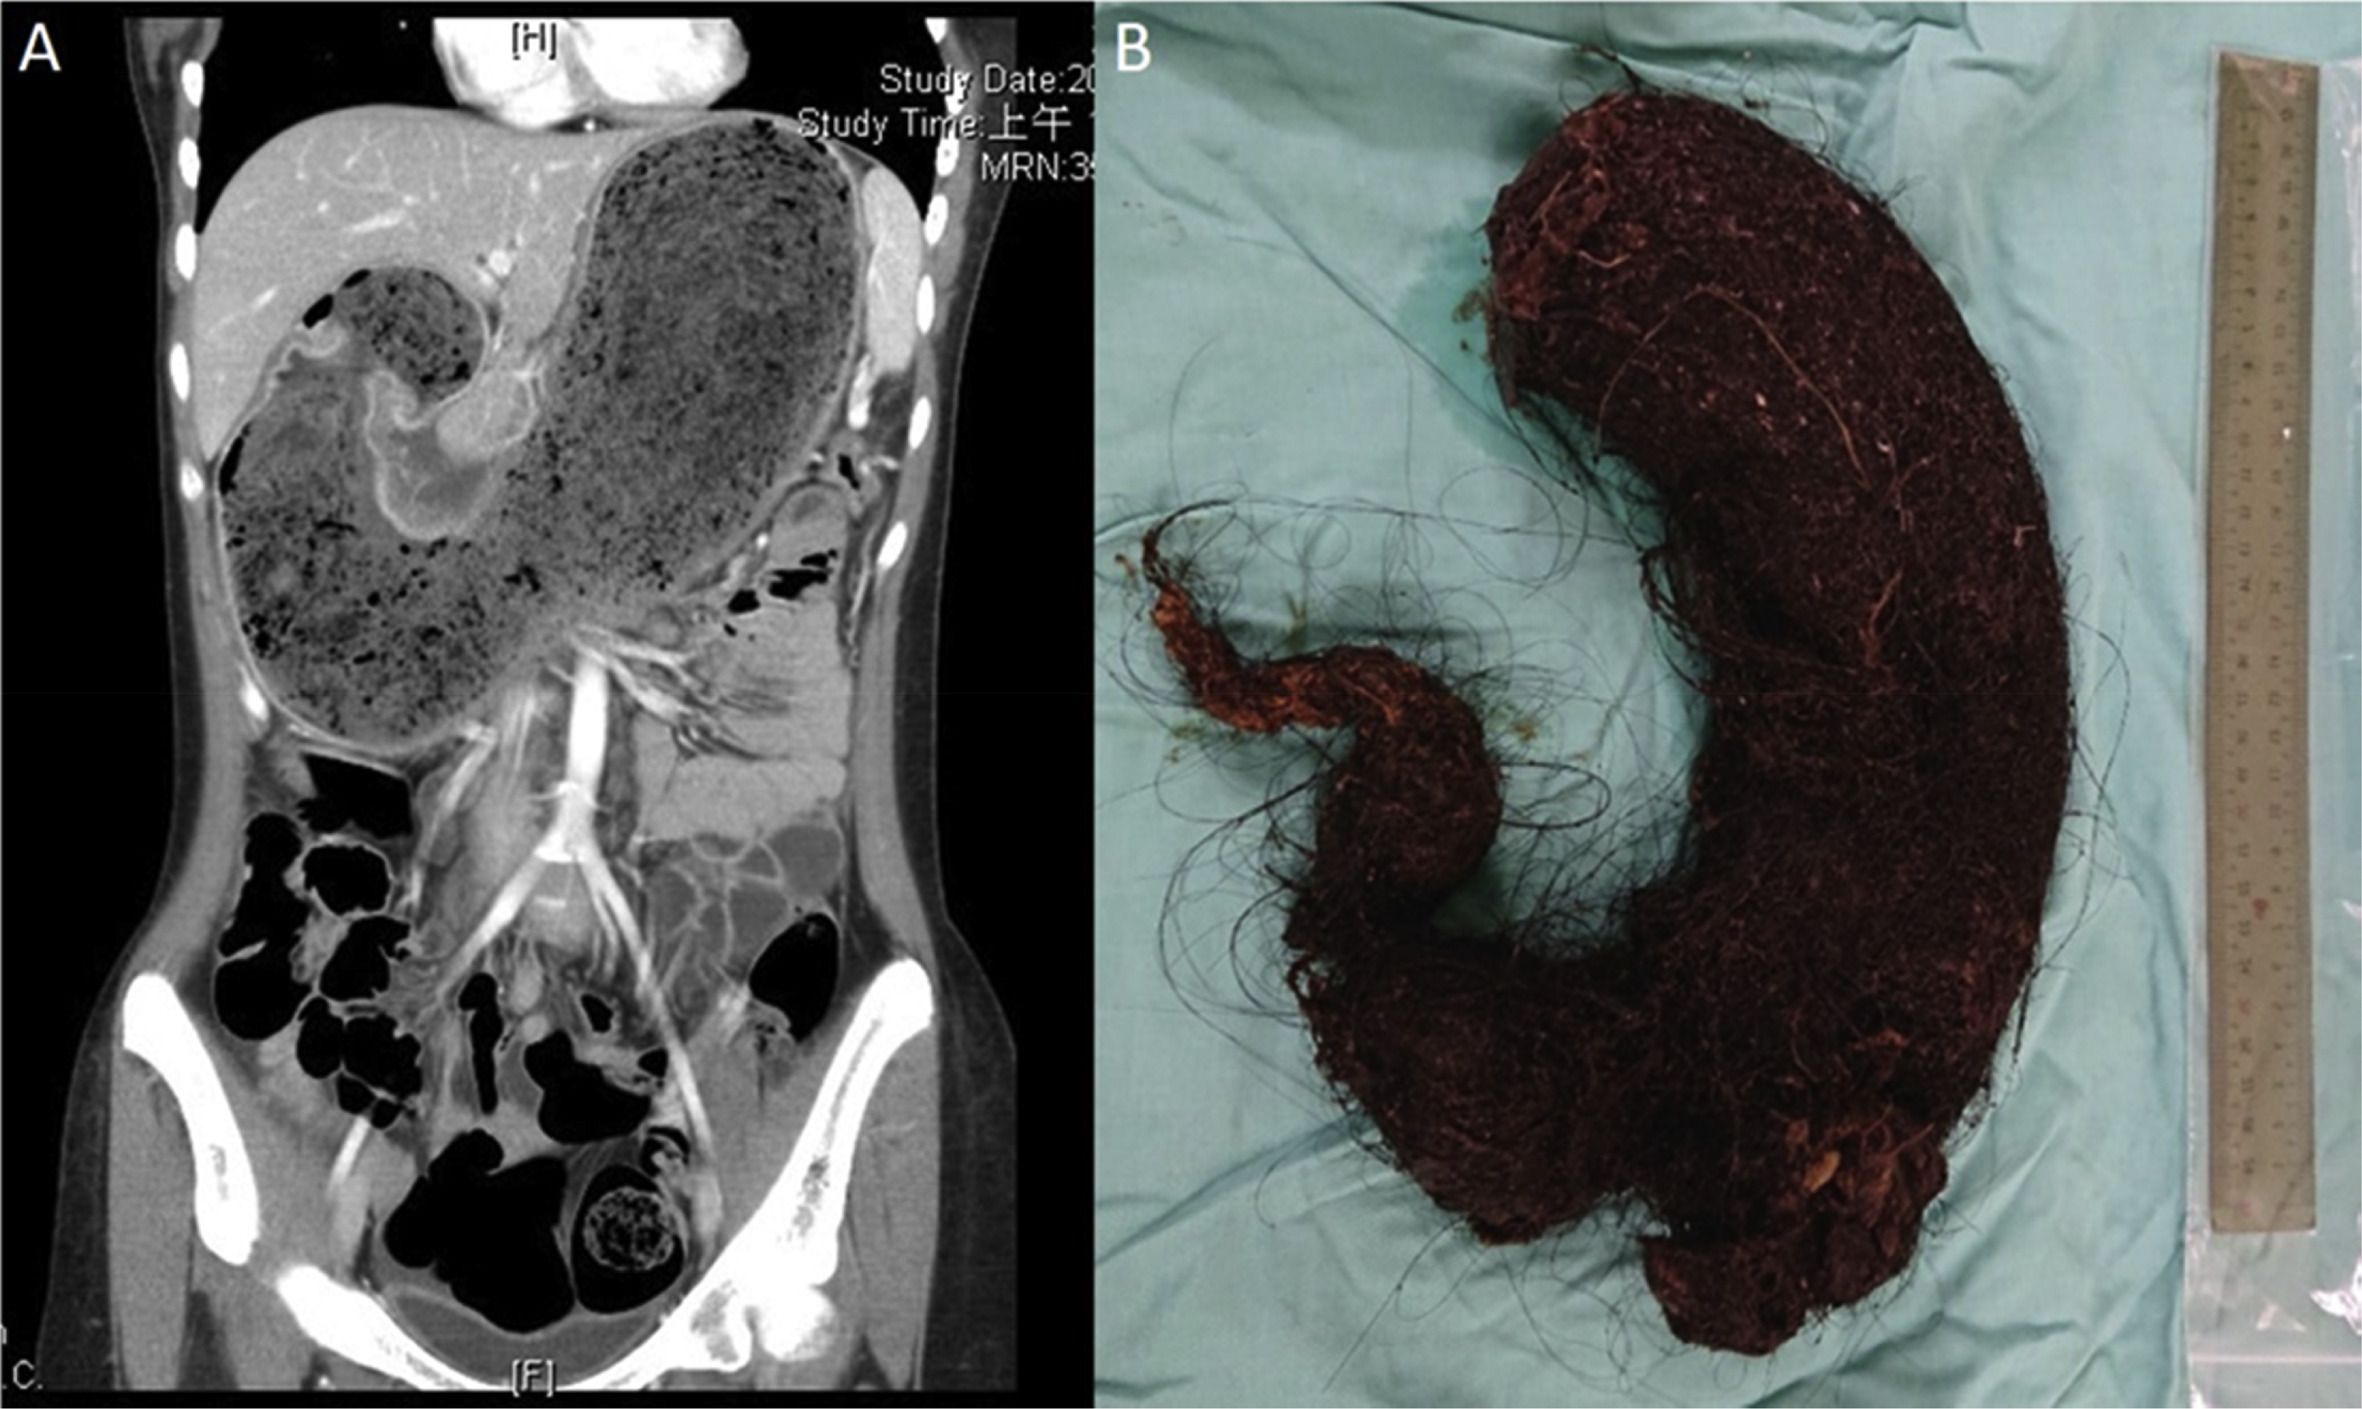

Rapunzel syndrome is also known as trichobezoar. It is a condition characterized by ingestion of hair which eventually leads to gastric outlet obstruction and other abdominal symptoms. Rapunzel syndrome is associated with trichotillomania, depression, body dysmorphism, trichophagia, and prior surgeries. Rapunzel syndrome presents with complaints of: - anorexia - weight loss - vomiting - alopecia - acute epigastric pain Reference: https://radiopaedia.org/articles/rapunzel-syndrome-1 Image via: https://www.pediatr-neonatol.com/article/S1875-9572(19)30520-0/fulltext